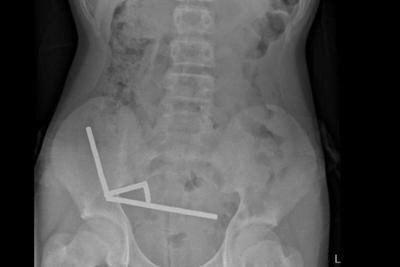

Scans showed that the magnets had formed four chains inside his abdomen, binding parts of the bowel together.